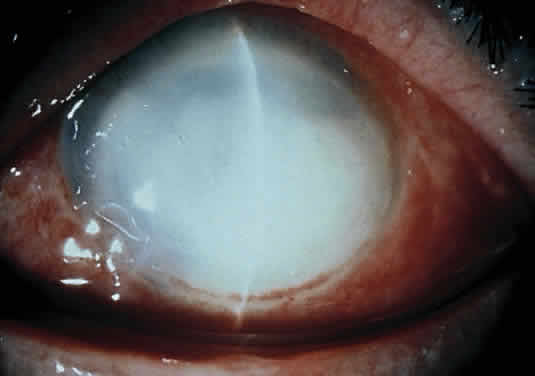

Clinically, the infected staphylococcal corneal ulcer presents with a yellow-white, well-demarcated area of infiltrate, which appears directly beneath an epithelial defect (Fig. 2). On occasion, multiple, small satellite lesions may develop. The infection may initially be superficial; however, if inadequately treated it can produce a mid to deep stromal abscess that may eventually lead to perforation. Stromal edema and white blood cell migration frequently surround the dense infiltrate and clear as the infection comes under control. Although there may be a marked anterior chamber reaction with hypopyon, the ulcer more frequently is indolent, with only a minimal inflammatory reaction.34